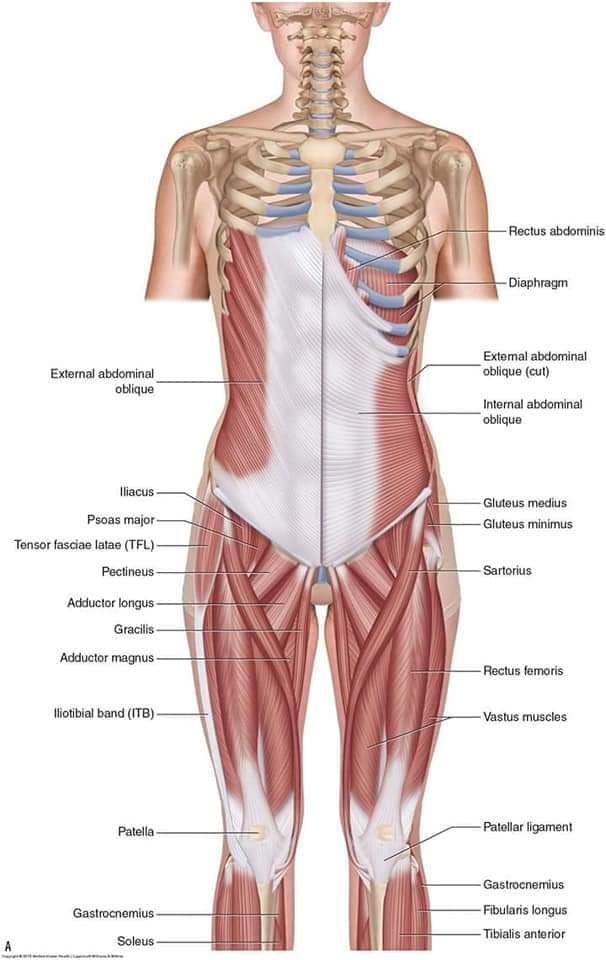

М'язова система людини є однією з основних систем організму, що відповідає за рухи, підтримання пози та стабільність. Вона складається з понад 600 м'язів, які можна класифікувати на скелетні, гладкі та серцеві м'язи. Скелетні м'язи, які є об'єктом нашого детального розгляду, дозволяють контролювати навколишній світ і виконувати різноманітні рухи. Особливу увагу в нашій статті буде приділено шейним і спинним м'язам, оскільки ці групи м'язів мають критичне значення для підтримання правильного постава та функціонування хребта.

Скелетні м'язи з'єднані з кістками за допомогою сухожиль і відповідають за більшість волевих рухів. Вони поділяються на:

- Швидкі м'язи - призначені для швидких і потужних рухів.

- Повільні м'язи - забезпечують стійкі і довготривалі рухи.

Скелетні м'язи мають поперечну смугасту структуру, що забезпечує їхню здатність до швидкого і ефективного скорочення.